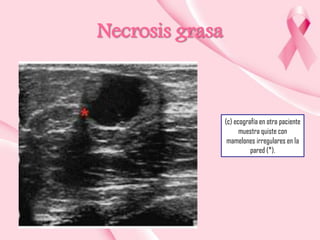

Necrosis grasa

(c) ecografía en otra paciente

muestra quiste con

mamelones irregulares en la

pared (*).